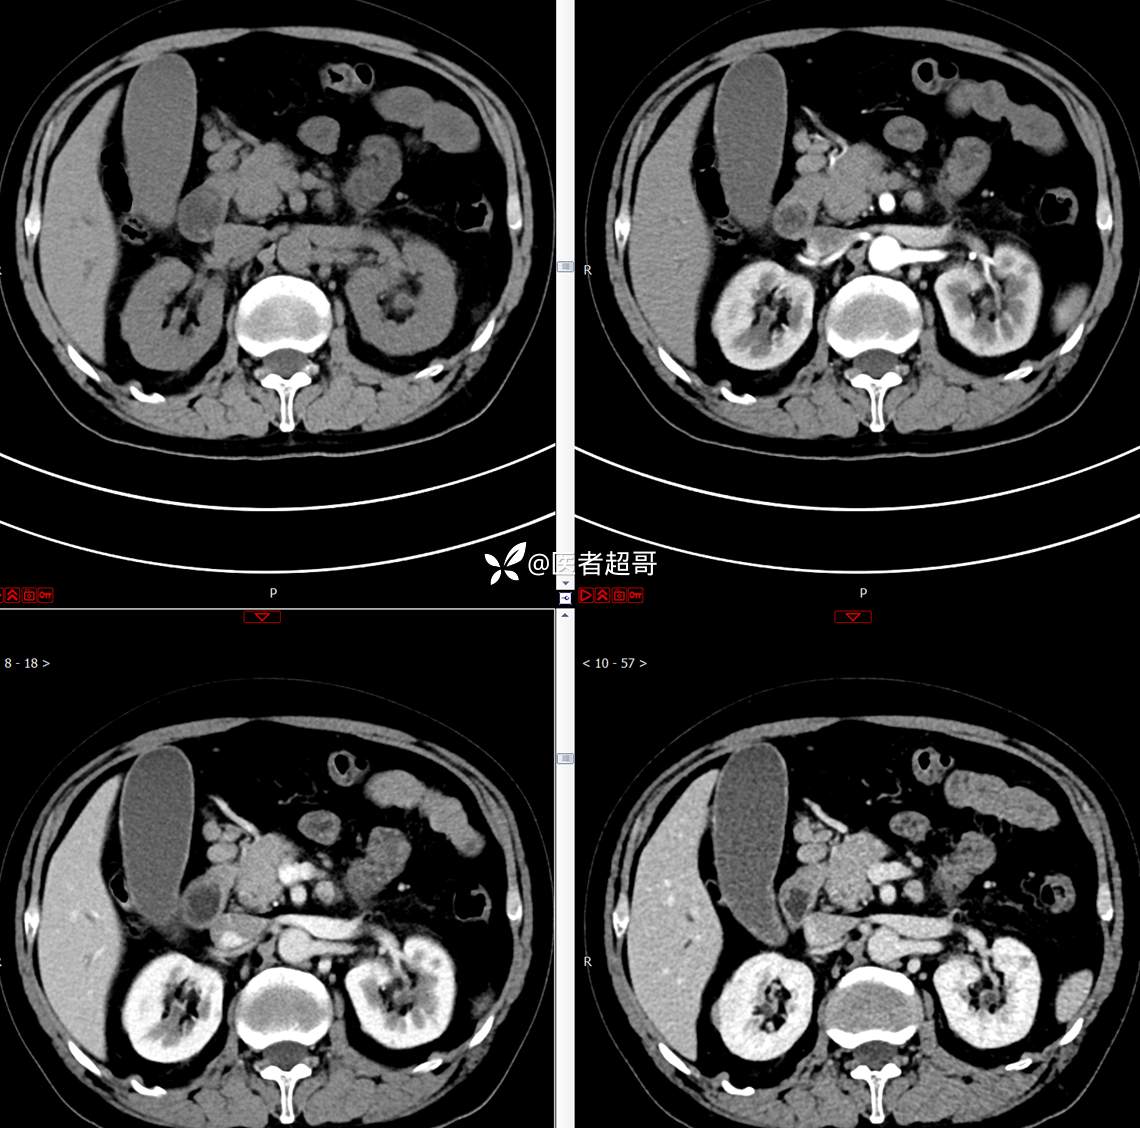

【影诊笔记772】腹痛就诊,发现肾脏病变,CT、MRI齐全,请高诊!

男,63岁 0200825 01

主 诉:间断腹痛15天

现病史:患者15天前无明显原因及诱因出现腹部疼痛不适,呈间断性钝痛,右下腹为著,无尿频、尿急、尿不尽,无发热、寒战,无腹胀。于市中心卫生院住院治疗,超声示:胰头低回声包块,胆系扩张,左肾囊肿,胆囊壁毛糙,胆囊内胆汁淤积。患者为求进一步诊治,遂以“肾盂肿瘤”收入院,患者自发病以来,神志清,精神可,饮食睡眠可,大便无明显异常,近期体重无明显增减。

既往史:既往体健